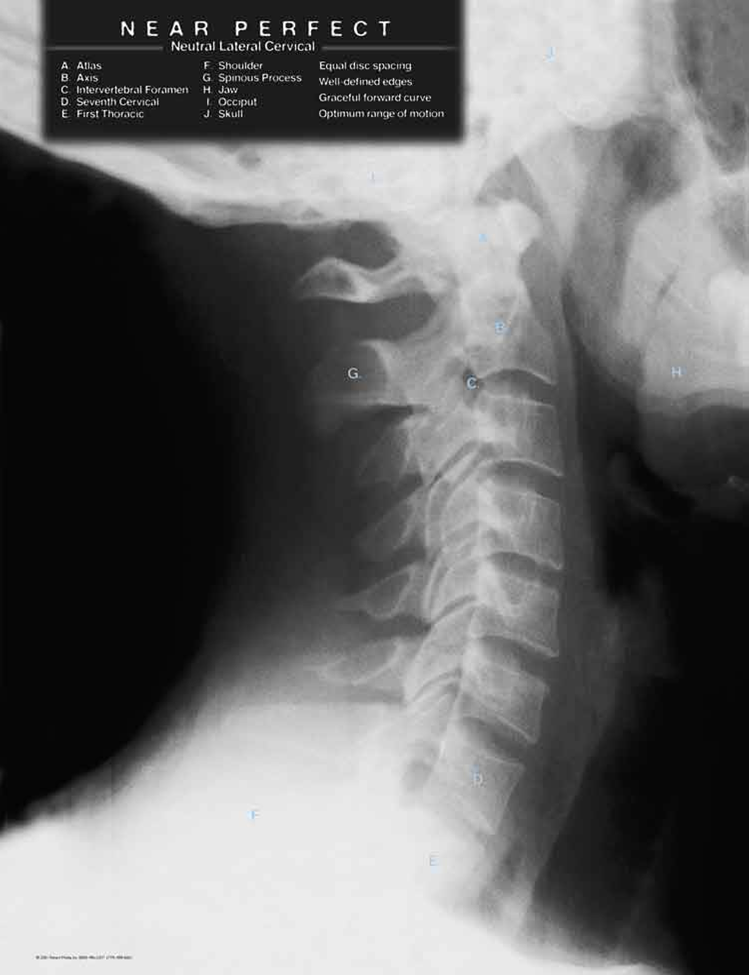

The diagnosis of cervical sprain is not difficult, but is most often derived from the mechanism of injury as described above. In this type of injury, there is such a rapid acceleration and deceleration of the head on the neck that the normal alignment of the vertebra is lost. When there is a typical C-shaped curve of the neck when viewed from the side, that curve can become reduced, straightened or reversed. The subsequent subluxations of the vertebrae, stretching of the ligaments and protective contraction of the muscles generate a tremendous amount of pain. Headaches are a frequent development following an injury of this type since the nerves that innervate the skull are often compressed and/or tractioned as a result.

One of the most common reasons for seeing a chiropractor is for this exact kind of injury. Usually a set of x-rays will help confirm a diagnosis of cervical spine sprain/strain. Gentle cervical adjustments are the best remedy for removing these subluxations of the spine while restoring nerve function and range-of-motion. Physical therapy modalities are often utilized in conjunction with care in order to help facilitate the healing process, either by reducing inflammation or calming muscle spasms. Stretching and exercises are introduced at the proper time. Depending on the condition, treatment and recovery times vary, ranging from 6 weeks to 6 months. Considering the involvement of the spine and nervous system, if the sprain is significant enough to cause a permanent problem, follow-up treatments may be recommended in order to help stabilize the affected area.